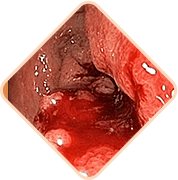

3 Riesgos graves de las hemorroides

Cualquiera de los siguientes

puede ser letal:

Las hemorroides pueden ocultar

enfermedades serias del recto:

- Lesiones

- Hemorragias intestinales

- Cambios necróticos

- Cáncer

Los vasos sanguíneos dilatados en las hemorroides pueden sufrir daños y romperse, aumentando el riesgo de hemorragia. La severidad de la hemorragia puede variar desde leve hasta severa, requiriendo cirugía o incluso transfusiones de sangre.

Las hemorroides crónicas pueden causar la formación de coágulos en los vasos sanguíneos. Con el tiempo, estos coágulos pueden desprenderse y obstruir los vasos de otros órganos internos, causando accidentes cerebrovasculares, embolia pulmonar y tromboembolia coronaria.